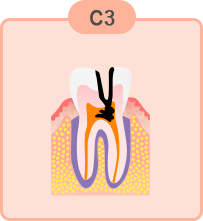

重度のむし歯

歯の神経近くまでむし歯が進行しています。